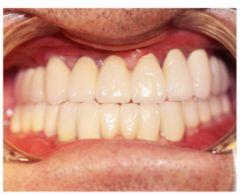

種植修復(fù)后照片

通過X光片可以看到,醫(yī)生雖然盡量設(shè)計(jì)連冠種植,但還是用了十七個(gè)植體,盡管已經(jīng)是多次調(diào)整后的精簡(jiǎn)方案,但手術(shù)時(shí)長(zhǎng)依然長(zhǎng)達(dá)一天。位老先生之前在另一家醫(yī)院咨詢時(shí),醫(yī)生給的方案是種二十二個(gè)植體,光是種植費(fèi)用就令人大呼“害怕”了。